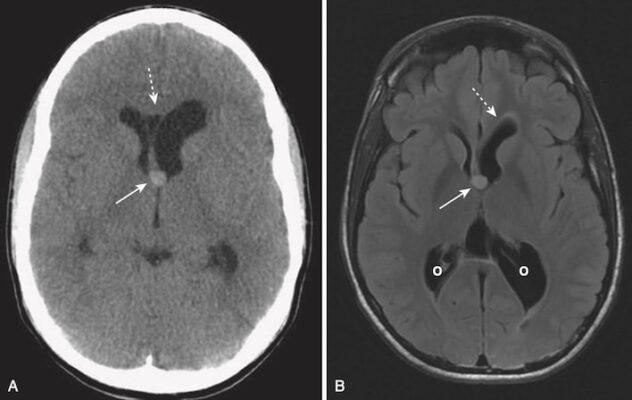

A, Chụp CT ở bệnh nhân này với các triệu chứng trong 2 giờ trước khi nghiên cứu là bình thường.

B, Chụp MRI khuếch tán trên cùng một bệnh nhân vài phút sau cho thấy một vùng có cường độ tín hiệu sáng bất thường ở vùng chẩm trán bên phải (mũi tên trắng). Hình ảnh khuếch tán (Diffusion-weighted imaging, DWI) là một chuỗi xung MRI có thể được thu nhận nhanh chóng và cực kỳ nhạy để phát hiện các bất thường trong chuyển động bình thường của nước trong não do đó có thể xác định đột quỵ trong vòng 20 đến 30 phút sau khi sự kiện xảy ra.